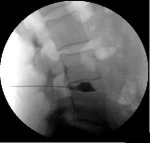

The procedure is done in a surgical center with fluoroscopic (x-ray) guidance. For lumbar discography it is done with you lying on your stomach. You will be given intravenous sedation to help you be comfortable and relaxed. You are watched closely with an EKG monitor, blood pressure cuff and blood oxygen-monitoring device. The skin over the injection site(s) is cleaned with an antiseptic solution and then the injections are performed.